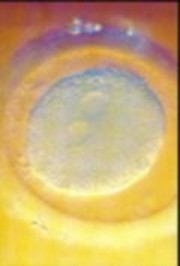

受精後8天。胚牙完成"著陸",微微嵌入子宮內膜。此時它分裂發育為幾百個細胞。